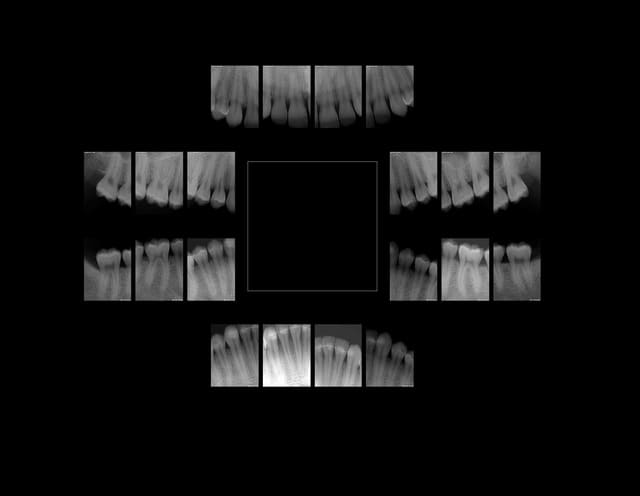

Moise 22 ans. Je fais quoi sur 36, 26 ? coiffages ?)))))

Moise 22 ans mjzhrh - Eugenol

Capture d  cran 2015 03 12 12.28 - Eugenol

chicot29

04/03/2013 à 17h24

Et c'est plusieurs fois par jour comme ca.